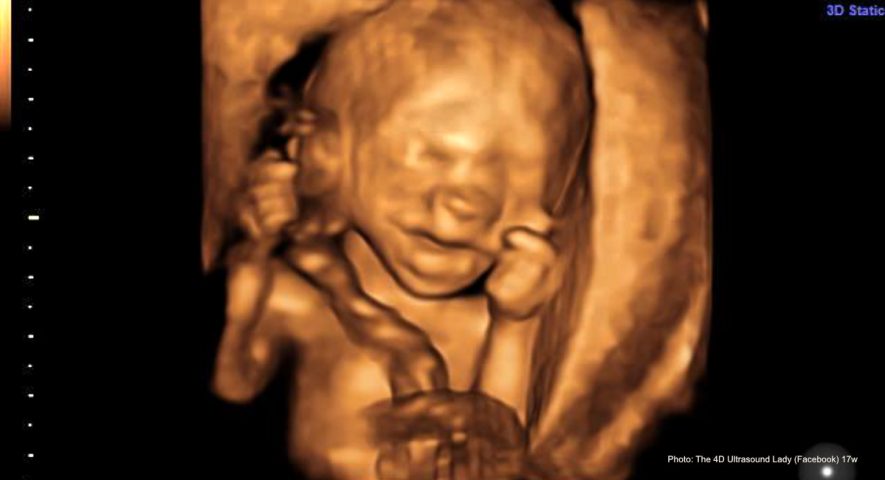

17-wks-gestation-4D-Ultrasound-Lady. Source: Live Action